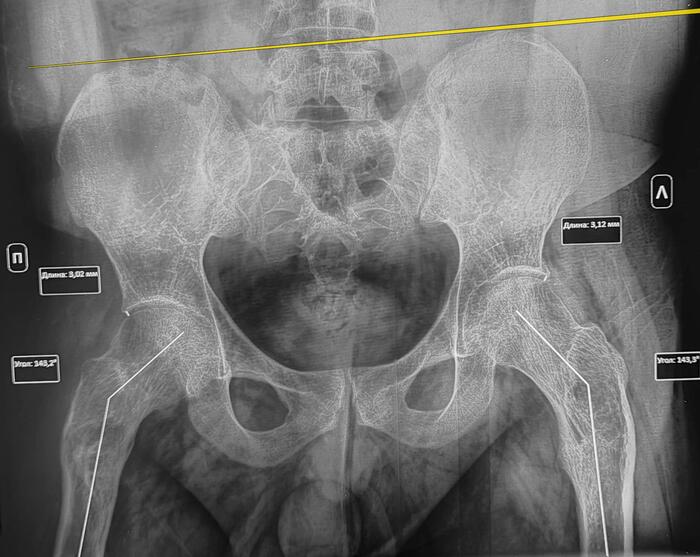

В анамнезе у призывника диагноз- дисплазия тазобедренных суставов, перенесенное оперативное лечение по поводу дисплазии в детстве. По данным рентгенографии костей таза: ШДУ справа 143 град, слева 143 град, сужение суставной щели справа до 3 мм, слева до 3.1 мм, остеофиты по верхне-наружным краям суставных щелей, шейка правой бедренной кости укорочена ,перекос таза вправо. Двусторонние участки разряжения костной ткани в межвертельной области(более выраженно справа)-как следствие перенесенных оперативных вмешательств. Заключение: Coxa valga bilateralis как следствие дисплазии тазобедренных суставов. Вторичный двусторонний коксартроз 1ст.